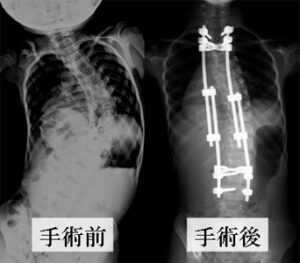

矯正するカーブの場所により方法を使い分けます。後方法は胸椎カーブ、胸腰椎カーブに適応されます。前方法は胸腰椎カーブ、腰椎カーブに適応されます。(図2)

手術方法は大きく分けて前方法(図3)と後方法(図4)の二つに分けられます。

(2)後方法 (図3、図4参照)

背中に縦の皮切を加えて、背骨から筋肉を剥がして棘突起、椎弓、横突起といった背骨の後方組織を露出します。

矯正に使用する機械は主に椎弓根スクリューとロッドを使用します。時によってはフックやワイヤーも使用します。(図5)

椎弓根にスクリューを設置し、そこにロッドを連結させて様々なテクニックを用いてカーブを矯正していきます。(図6)